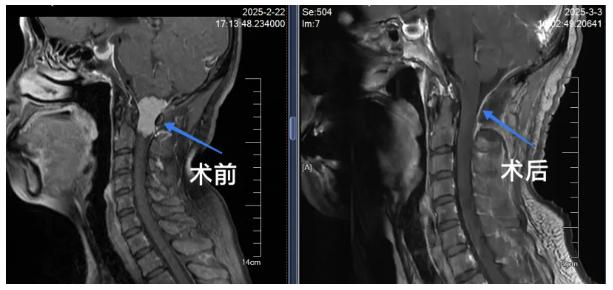

患者熊女士两年前开始出现反复头颈部疼痛,初期按“颈椎病”治疗。去年11月份症状急剧加重,出现手脚麻木、肌力下降及行走不稳等神经压迫症状。通过3.0T磁共振增强扫描及CT三维血管重建等精准检查,诊断为颅颈交界区髓外硬膜下肿瘤,病灶与脑干、椎动脉、颈神经等重要结构紧密相邻。

2月28日,在湖北省人民医院简志宏教授指导下,团队采用枕下远外侧入路实施肿瘤全切术。手术在机器人显微镜下精细操作,配合术中实时神经电生理监测,历时5小时成功全部切除病变。整个手术过程顺利,出血量少,患者生命体征平稳。术后转入神经外科监护室,护理人员实施24小时专人监护,同步开展早期康复介入。